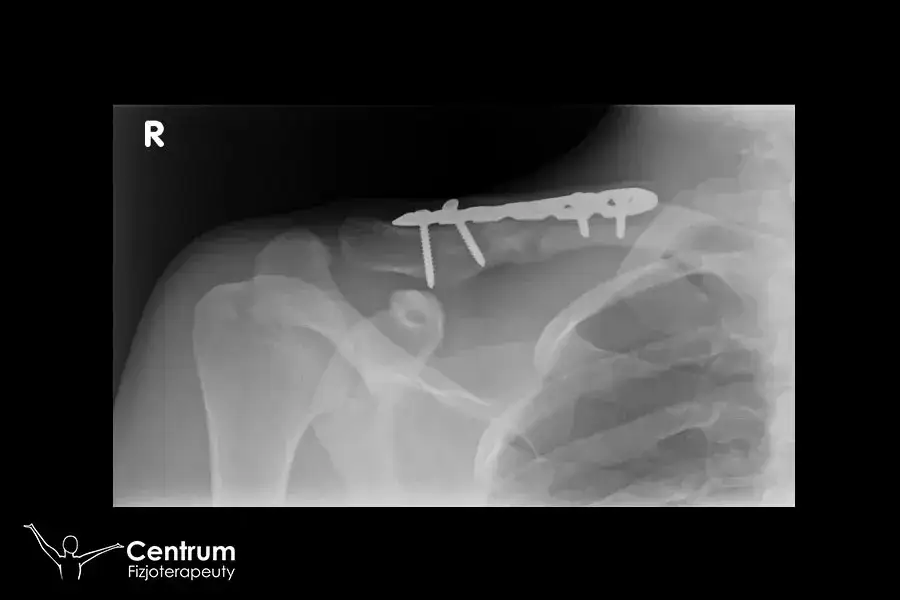

Skierowanie na rezonans magnetyczny jest często konieczne w przypadku różnych schorzeń ortopedycznych i neurologicznych. Takie badanie pozwala lekarzom na dokładną diagnostykę problemów zdrowotnych, które mogą być trudne do zidentyfikowania za pomocą innych metod. Wśród pacjentów z dolegliwościami bólowymi, urazami czy przewlekłymi schorzeniami, rezonans magnetyczny może dostarczyć kluczowych informacji o stanie tkanek, stawów oraz struktur mózgowych. Warto wiedzieć, jakie konkretne schorzenia mogą wymagać skierowania na to badanie, aby móc skutecznie zdiagnozować i leczyć pacjentów.

- Urazy stawów – takie jak skręcenia, zwichnięcia czy uszkodzenia więzadeł, które mogą wymagać dokładnej oceny stanu stawu.

W diagnostyce medycznej, rezonans magnetyczny odgrywa kluczową rolę w identyfikacji wielu schorzeń. Przykłady schorzeń ortopedycznych obejmują urazy stawów, takie jak uszkodzenia więzadeł krzyżowych w kolanie, które mogą być trudne do zdiagnozowania bez obrazowania. W neurologii, rezonans jest niezbędny do oceny stanów takich jak stwardnienie rozsiane, gdzie zmiany w obrębie mózgu są kluczowe dla postawienia diagnozy. Obrazowanie MRI dostarcza szczegółowych informacji, które pomagają lekarzom w opracowaniu skutecznych planów leczenia.

| Uszkodzenie więzadła krzyżowego | Ból kolana, obrzęk, ograniczona ruchomość | Wizualizacja uszkodzeń i ocena stabilności stawu |